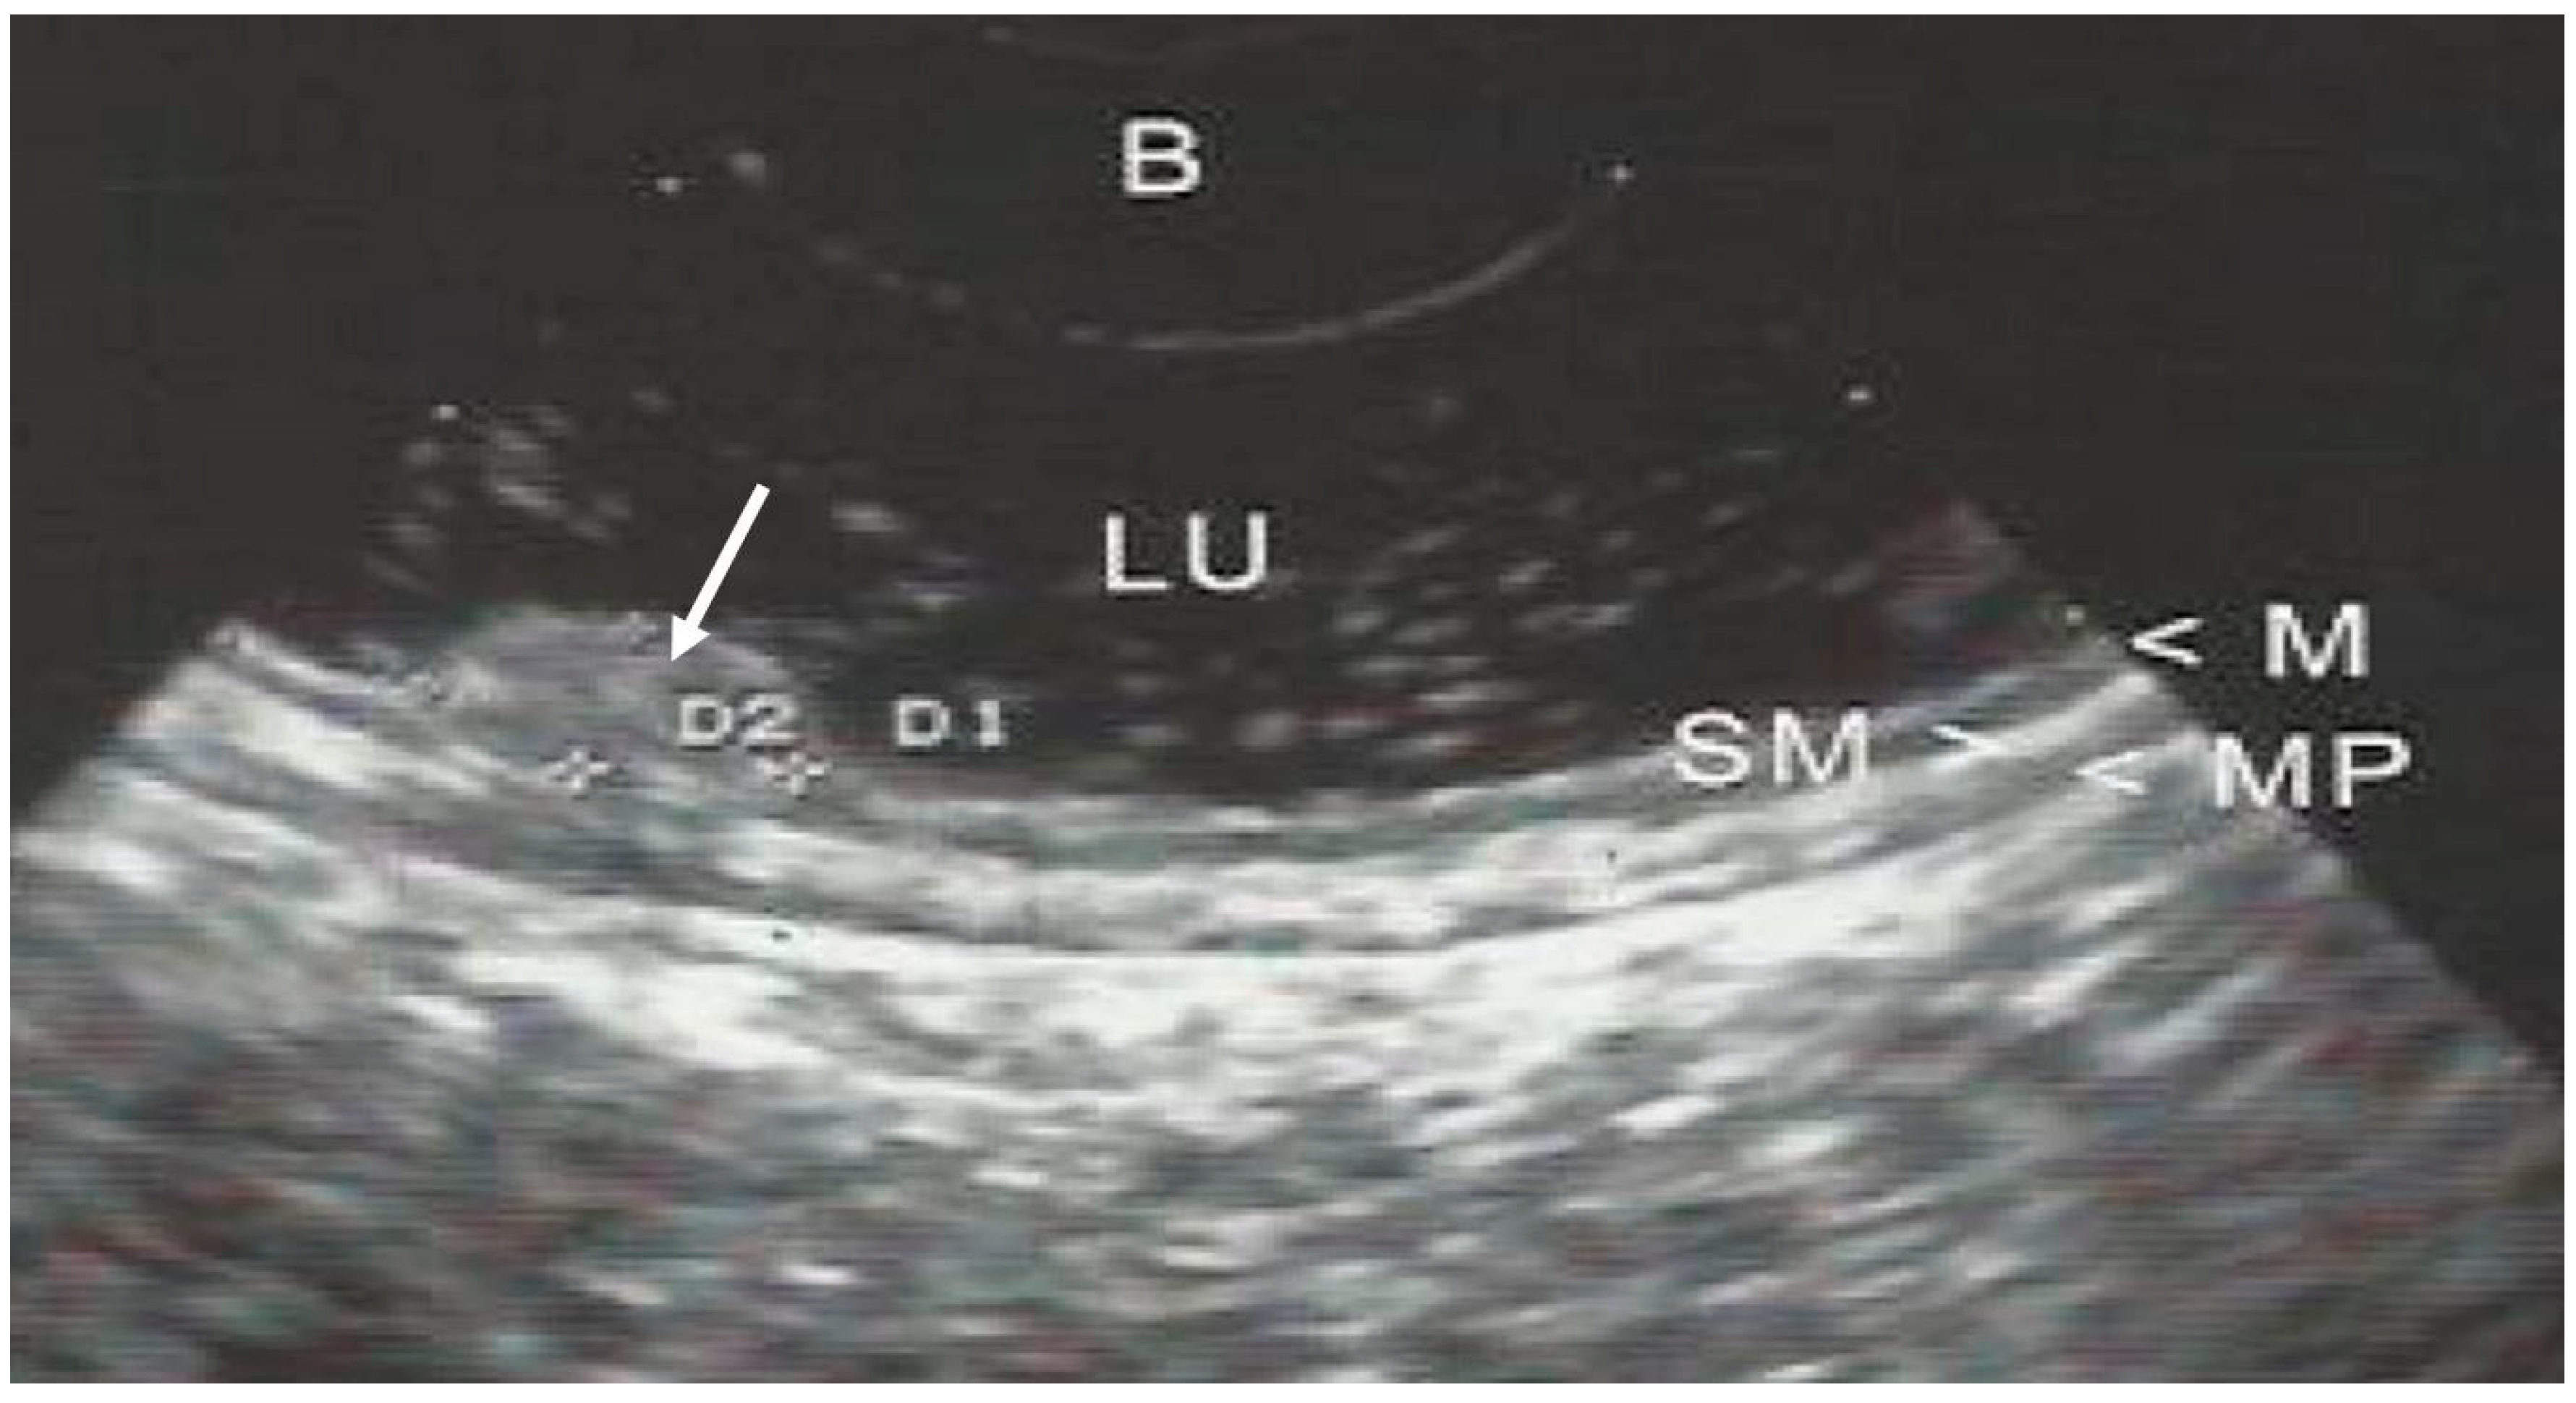

| EUS layer invasion | Mucosa | 155 (52.9) |

| Submucosa | 32 (10.9) | |

| Proper muscle | 32 (10.9) | |

| Subserosa | 74 (25.3) | |